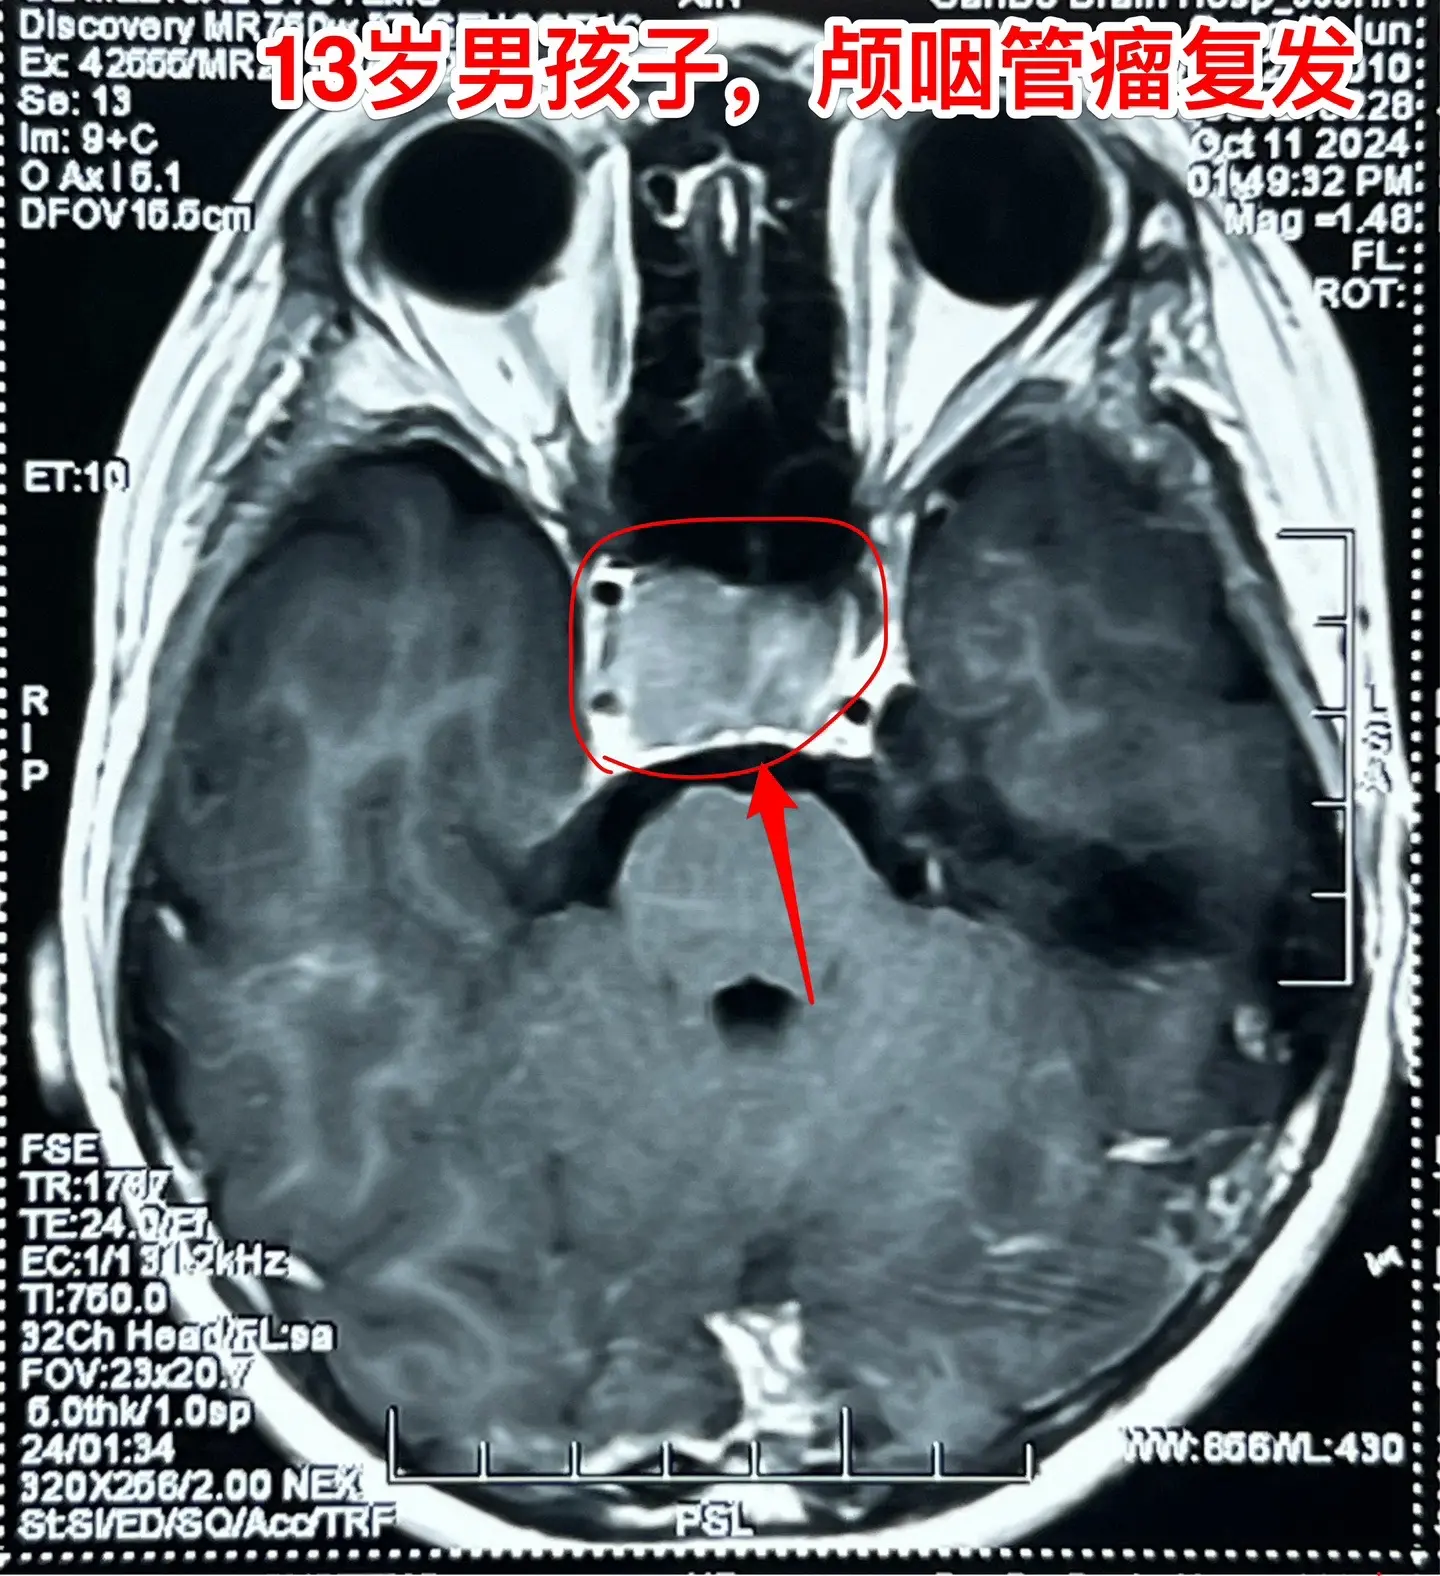

鞍隔下型颅咽管瘤经翼点入路切除合适吗?13岁的山东省菏泽市男孩子,九年...